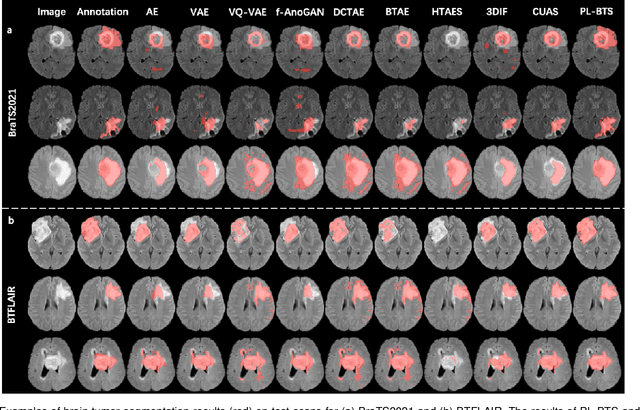

Abstract:Automated brain tumor segmentation based on deep learning (DL) has achieved promising performance. However, it generally relies on annotated images for model training, which is not always feasible in clinical settings. Therefore, the development of unsupervised DL-based brain tumor segmentation approaches without expert annotations is desired. Motivated by the success of prompt learning (PL) in natural language processing, we propose an approach to unsupervised brain tumor segmentation by designing image-based prompts that allow indication of brain tumors, and this approach is dubbed as PL-based Brain Tumor Segmentation (PL-BTS). Specifically, instead of directly training a model for brain tumor segmentation with a large amount of annotated data, we seek to train a model that can answer the question: is a voxel in the input image associated with tumor-like hyper-/hypo-intensity? Such a model can be trained by artificially generating tumor-like hyper-/hypo-intensity on images without tumors with hand-crafted designs. Since the hand-crafted designs may be too simplistic to represent all kinds of real tumors, the trained model may overfit the simplistic hand-crafted task rather than actually answer the question of abnormality. To address this problem, we propose the use of a validation task, where we generate a different hand-crafted task to monitor overfitting. In addition, we propose PL-BTS+ that further improves PL-BTS by exploiting unannotated images with brain tumors. Compared with competing unsupervised methods, the proposed method has achieved marked improvements on both public and in-house datasets, and we have also demonstrated its possible extension to other brain lesion segmentation tasks.